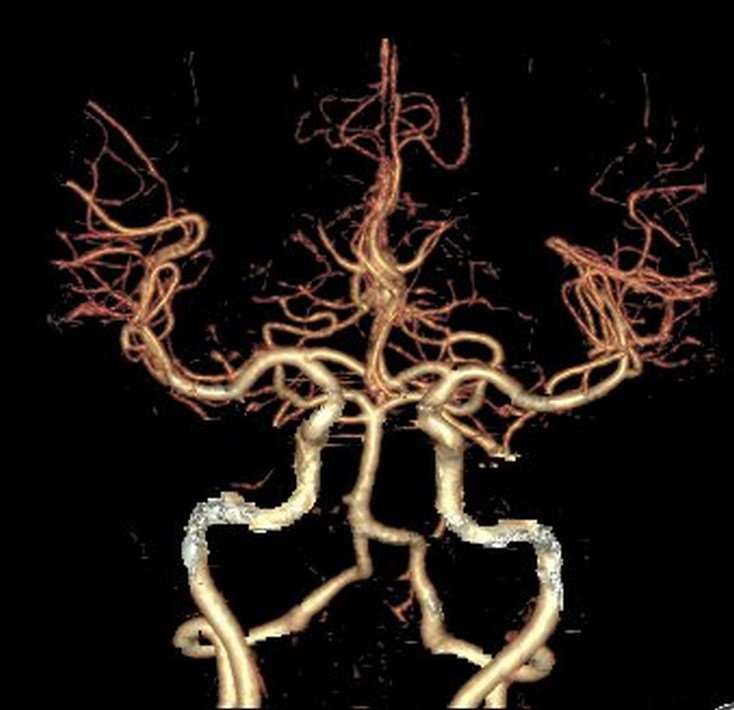

Brain Angiography